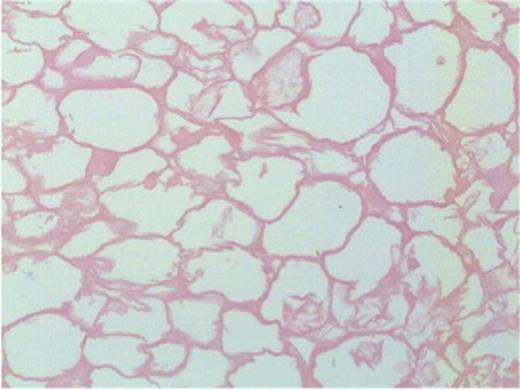

Microscopically, both nodules showed similar histological features. The larger nodule required prolonged, gentle decalcification before reasonable tissue sections could be obtained. Each had a thick shell of dense paucicellular collagen arranged as concentric layers with only a few fibroblasts and inflammatory cells present peripherally (Figures 4b and 5). The shell was devoid of cartilage and it encased necrotic adipose tissue (Figure 6) in which there was focal dystrophic calcification. No granulomatous inflammation, lung parenchyma, abscess formation, caseous type necrosis or neoplasm was identified.

Necrotic adipose tissue centrally within the nodule (200x magnification)